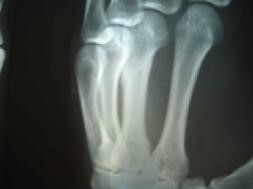

此前,二零零二年五月二十八日,邢家秋在钢屯镇虹螺山发真相,被当地派出所绑架,遭到钢屯恶警昼夜酷刑折磨后,被投入葫芦岛市看守所。七月被非法秘密判刑六年,九月被投入沈阳第三监狱(沈阳监狱城)迫害。二零零三年大年过后,邢家秋遭强制“转化”,恶警指使犯人王权强制他面壁罚站,每天被迫面壁而立十二小时,稍有不从就会招来一顿毒打。他的腿严重受伤,不能正常走路。

二零零三年三月,邢家秋不堪残酷的摧残,以绝食抗议。在监区队长王晓波、董仑山的指使下,犯人王权、李素安等人在操作间里对他进行围殴。李素安找来一根铁锹把儿,犯人们把他摁倒在地,扒下他的棉裤,分别踩着、摁着他的头、腿、胳膊,李素安抡起锹把猛烈抽打他的腰、臀等部位。因为剧痛,邢家秋用手去挡,手却被李素安抡了一棒,他晕了过去,这时,他的手背肿得像个馒头,不能动。第二天,李素安、金永军对他又一顿毒打,李素安冲着他受伤的手砍了一掌,他痛得坐在地上,此后他的手剧烈疼痛不敢动。

二零零五年六月在沈阳第一监狱拍的X光片子显示邢家秋左手中指骨折